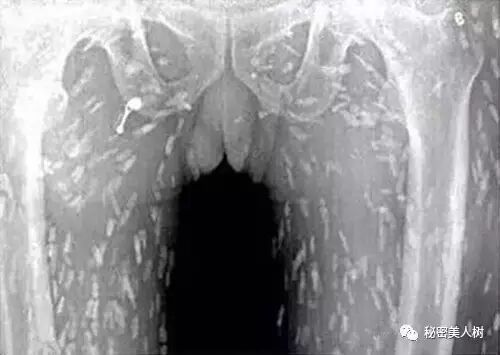

来张图刺激刺激你

请忍住恶心看完

吐~ing

《温州日报》曾报导,温州瑞安县有某位患者因为吃了生鱼片,导致全身长满寄生虫。X光照片显示:患者的手臂和肺部都是呈白色椭圆形小点的寄生虫。让人看了头皮发麻。

医生诊断为他是因为吃了太多生鱼片,才会有如此严重的感染。